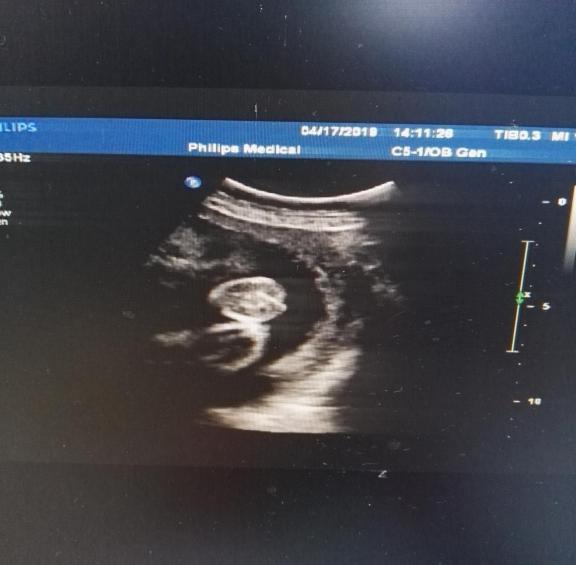

F2胎儿超声测值:

双顶径 75mm,头围 289mm,腹围243mm,股骨长 54mm,最大羊水深度 53mm,羊水内见一条带样高回声漂浮。

胎心率 156次/分,胎盘位于后壁,厚约31mm。

阳性指征:探查时胎儿外生殖器呈“郁金香”征。

超声提示:胎儿外生殖器呈“郁金香”征(待排),建议复查